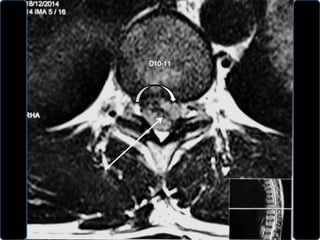

• A MRI was done.

• There was a disc extrusion at D10 – D11.

• The extruded fragment was on left side.

December 2014